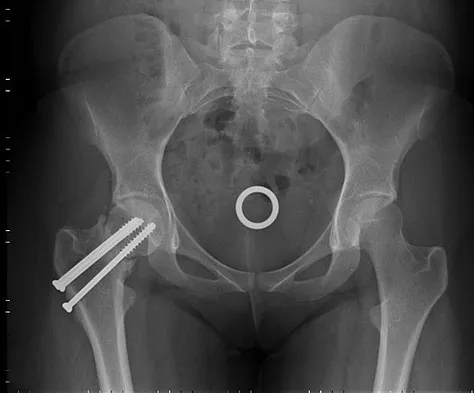

A 26-year-old woman sustained a nondisplaced femoral neck fracture and treatment consisted of use of percutaneous cannulated screws. At her 3-month follow-up visit, she reports hip pain and is unable to ambulate. A radiograph is shown in Figure 1. What is the next most appropriate treatment?

Femoral neck fracture nonunion is a challenging problem for orthopaedic surgeons. Vertical fractures are more prone to nonunion due to shear stress rather than compressive forces across the fracture site. Several authors have suggested these fractures are more common in young adults due to injury type and bone composition. It is widely regarded that an effort should be made to salvage the femoral head if vascularity remains. The most common method to treat this complication is valgus intertrochanteric osteotomy of the femur. This functionally makes a vertical fracture more horizontal, converting shear into compressive forces. It also helps correct the varus position of the fracture nonunion. Hartford JM, Patel A, Powell J: Intertrochanteric osteotomy using a dynamic hip screw for femoral neck nonunion. J Orthop Trauma 2005;19:329-333.